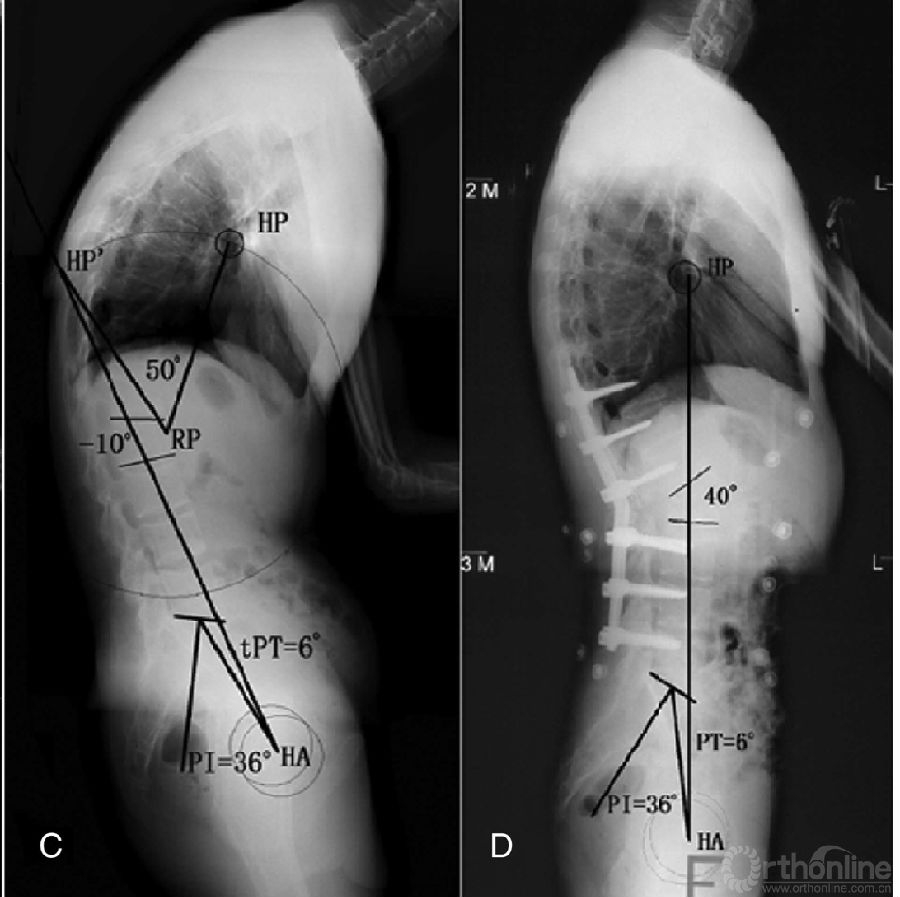

双节段截骨角度确定方法类似单节段,如下图。

图6双节段截骨角度的确定步骤和方法